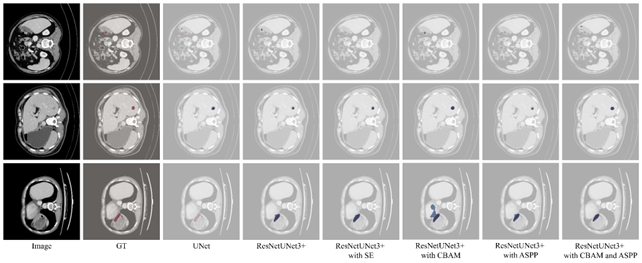

Table 5 presents seven metrics as Mean±StandardMean\pm Standard Deviation. The P-value indicates the statistical significance of the Dice score difference compared to the baseline (ResNetUNet3+) using the Wilcoxon signed-rank test. Cases where the model failed to predict any tumor mask (Dice = 0) were excluded from the HD95 average to prevent undefined infinity values. The integration of the CBAM module yielded the most robust performance, achieving the highest nominal Dice score (0.755±0.2680.755\pm 0.268) and IoU (0.662±0.2610.662\pm 0.261). Although the improvement in the mean Dice score compared to the baseline was not statistically significant (p = 0.287), the CBAM variant demonstrated superior model stability, evidenced by the lowest standard deviation among all tested configurations (0.268 vs. 0.284 for baseline). This suggests that jointly modeling channel- and spatial-wise dependencies helps reduce performance variance, allowing the network to maintain consistent segmentation quality across diverse samples. In contrast, the addition of ASPP alone resulted in a statistically significant degradation in performance (p < 0.001), with the mean Dice score dropping to 0.735±0.2950.735\pm 0.295. This indicates that the multi-scale context aggregation provided by ASPP may introduce noise or redundant features in this specific architecture, disrupting the precise boundary delineation required for small liver tumors. When combining ASPP with CBAM, the performance recovered (0.753±0.2750.753\pm 0.275), but did not surpass the CBAM-only configuration, confirming that the additional complexity of ASPP offers no distinct advantage over CBAM’s feature refinement. To further investigate the distribution of errors, we analyzed the box plots of the Dice scores (7). A notable observation is the presence of outlier cases where the Dice score drops to near zero across all models.

A notable observation is the presence of a long tail of outliers where the Dice score drops to near zero across all model variants. To understand the pathology behind these failures, we extracted representative samples corresponding to these outliers, as shown in Fig. 8. These cases illustrate extremely diminutive size and disjointed (non-clustered) tumor morphologies that lead to near-zero Dice scores.

Refer to caption

Figure 8: Visualization of hard example outliers of ResNetUNet3+ with CBAM. The predicted and groundtruth are highlighted in blue and red, respectively.